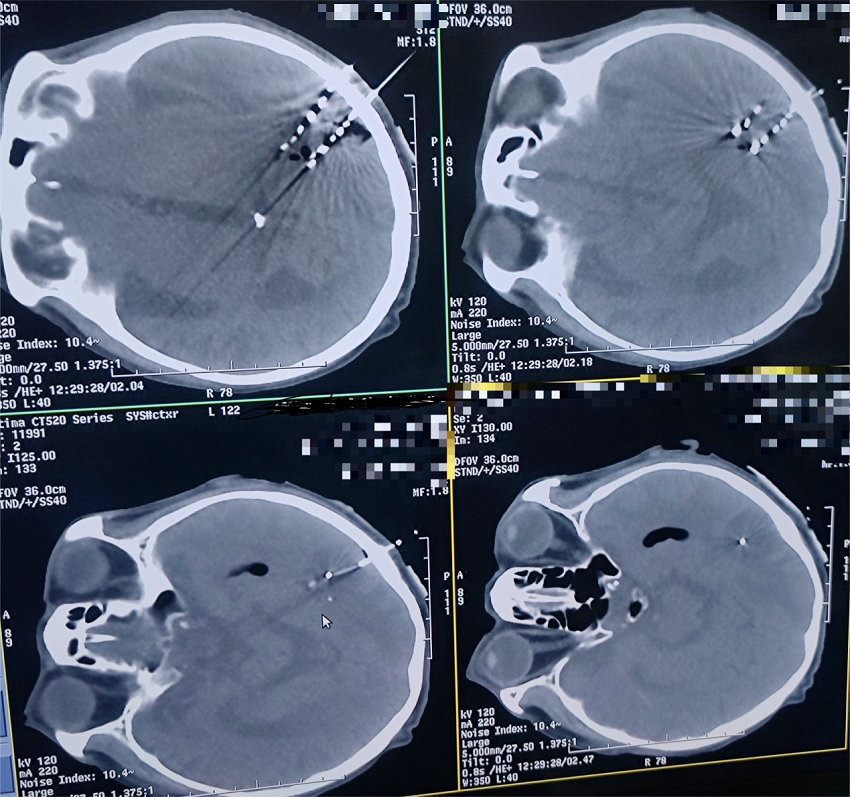

碘-125放射性粒子3D打印模版在颅脑肿瘤碘-125植入术

手术中